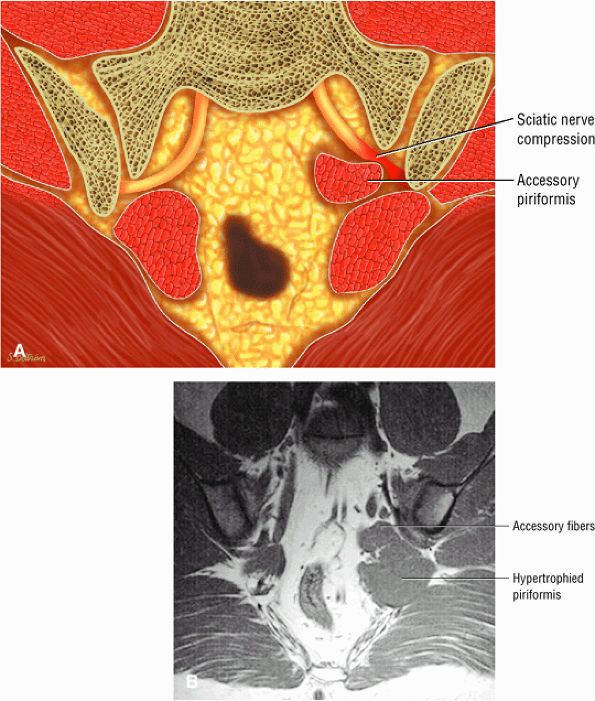

-

Entrapment of the sciatic nerve at this location may be associated with the piriformis syndrome. Asymptomatic hypertrophy of the piriformis muscle in this syndrome is best appreciated on axial images. The piriformis originates from the anterior sacrum and greater sciatic notch and inserts on the upper border of the greater trochanter. The piriformis divides the greater sciatic foramen into superior and inferior portions.